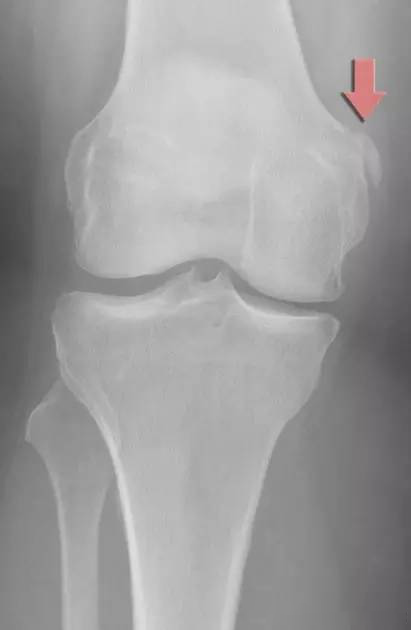

(5)Segond、反 Segond 骨折

Segond 骨折:胫骨平台前外侧撕脱骨折,多因为下肢过度内翻加内旋暴力所致,常伴有前交叉韧带、内外侧半月板的损伤。

A. 膝关节 X 线前后位片,胫骨平台外侧缘撕脱椭圆形小碎骨片,长轴平行于胫骨,见侧囊征(箭头);B. 同一患者 MRI 冠状位 PDWI SPAIR 显示胫骨平台外侧缘撕脱骨折(细箭头),内外侧半月板内横形高信号,提示损伤(粗箭头);C. 矢状位 PDWI SPAIR 中间层面 PCL 显示肿胀,信号不均,提示 PCL 水肿,呈轻度损伤(箭头)